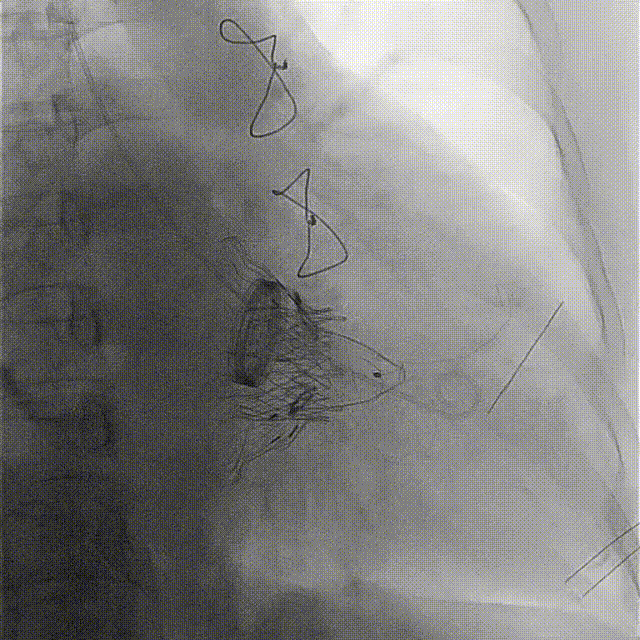

術前DSA

術后DSA